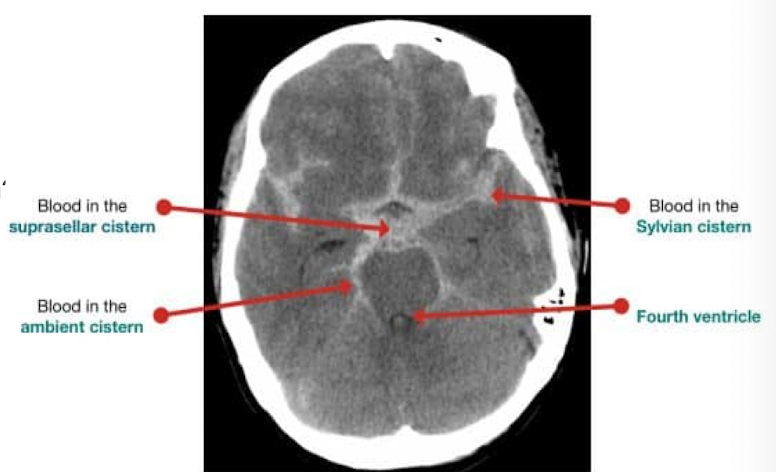

11

Q

where is the blood

A

subarachnoid (cisterns/circle of willis)

12

What to check when evaluating cisterns on CT

are they open and do they have blood in them